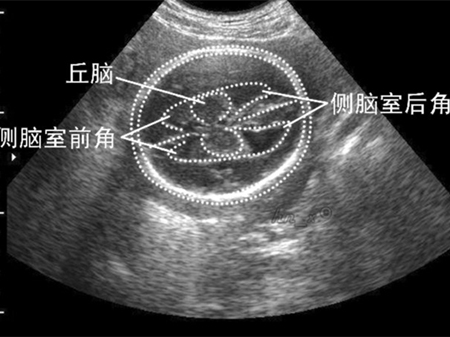

双侧侧脑室

双侧侧脑室,侧脑室位置图片

约40%的病例为双侧轻度侧脑室增宽

侧脑室位置图片

侧脑室后角

侧脑室增宽